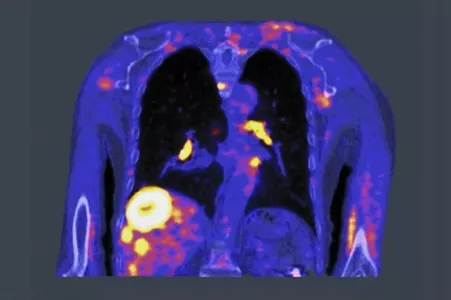

Radiotherapy uses high doses of radiation to kill cancer cells and shrink tumors. It’s performed after imaging scans such as positron emission tomography (PET), magnetic resonance imaging (MRI), or computed tomography (CT) locate the target tumors. Those images help medical professionals decide where to aim the radiation beam and determine the treatment field. But because the process requires two steps, doctors are forced to add a margin of error around the tumor.

Dr. Samuel Mazin set out to change that when he cofounded RefleXion in 2009, using his work on PET-based algorithms as a starting point. RefleXion is developing technology that would change the two-step image-then-treat process to a single step. It has developed a biology-guided radiotherapy (BgRT) platform that combines a well-established cancer imaging technique, PET, and radiation therapy.

Their beam shaping device, called a multi-leaf collimator, needed to be designed from scratch. The RefleXion team used Simulink® from MathWorks to test out their ideas easily and efficiently before building the device. This approach saved the team time and resources.“An elegant feature of BgRT is that its treatment advantages will not just apply to one tumor,” says Shirvani. “A single PET injection can generate the same homing signal at multiple tumors, which opens up the possibility of head-to-toe treatment of numerous metastatic sites in those with advanced disease.”

A well-known rule in cancer treatment is “the earlier, the better,” but sometimes symptoms are so subtle that catching the disease in its early stages can be very difficult. BgRT could help widen the treatment window for patients with advanced cases by treating all of the metastases in one session. “This could allow physicians to explore whether eradicating all metastases with radiation can improve survival or even result in durable remission for some patients,” says Shirvani.